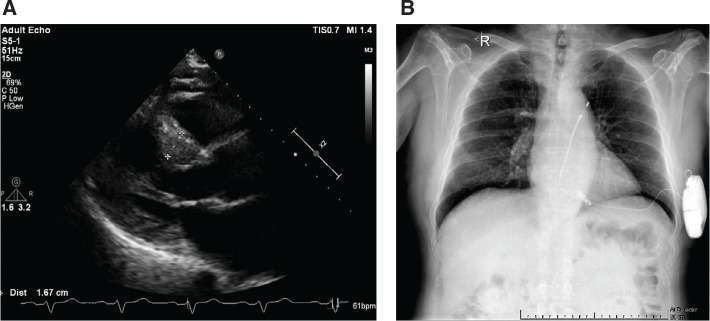

Cardiac implantable electronic devices (CIEDs) are essential tools in cardiology for tackling rhythm disturbances and have come a long way over the last decades. Technology is shifting toward leadless devices that spare the complications and limitations of traditional intravascular CIEDs. Herein, we report the simultaneous implantation of a leadless pacemaker (LP) and a subcutaneous implantable cardioverter-defibrillator (S-ICD) in two patients with hypertrophic cardiomyopathy, as well as their 2-year follow-up results, while explaining the preventive measures taken to steer around unwanted device interaction. Implantation of an S-ICD with an LP is reserved for unique cases but is a feasible approach when there is a contraindication for intravascular CIED implantation. Furthermore, this technique may be used in younger patients with cardiomyopathies in whom multiple generator replacements are expected, along with their known adverse effects.